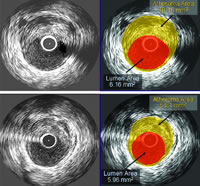

编者按 在清华大学、中华中医药学会共同主办的超微粉技术应用于现代特色中药成果发布暨学术报告会上,山东大学齐鲁医院张运院士报告了近十年来他们对动脉粥样硬化(AS)机制和干预研究的成果并介绍了国际上的最新研究结果。张运院士称,ASTEROID试验证明,低密度脂蛋白胆固醇(LDL-C)水平降得越低,斑块缩小越明显,如果有很好的药物治疗,AS是可以治愈的。PROVE IT-TIMI22研究结果显示,只有当LDL-C<70 mg/dl,同时高敏C反应蛋白(hsCRP)<2 mg/L时,患者预后才能最好,证明AS的发病是血脂和炎症因素等共同作用的结果。不同个体存在AS易患性基因差异,这些基因在环境因素和其他因素作用下发生了改变,从而导致AS发生。张运院士等对中药通心络稳定易损斑块,防止斑块破裂作用进行的研究结果显示,复方中药通心络的多靶点作用可能较好地弥补西药作用的单一性。

动脉粥样硬化脂质浸润学说的提出是因为研究者看到斑块中的脂质沉积,认为这是血液中脂质水平增高而渗透到血管壁内所致。有关他汀类药物临床试验中低密度脂蛋白胆固醇(LDL-C)水平与冠心病事件的关系研究支持了脂质浸润学说 ......